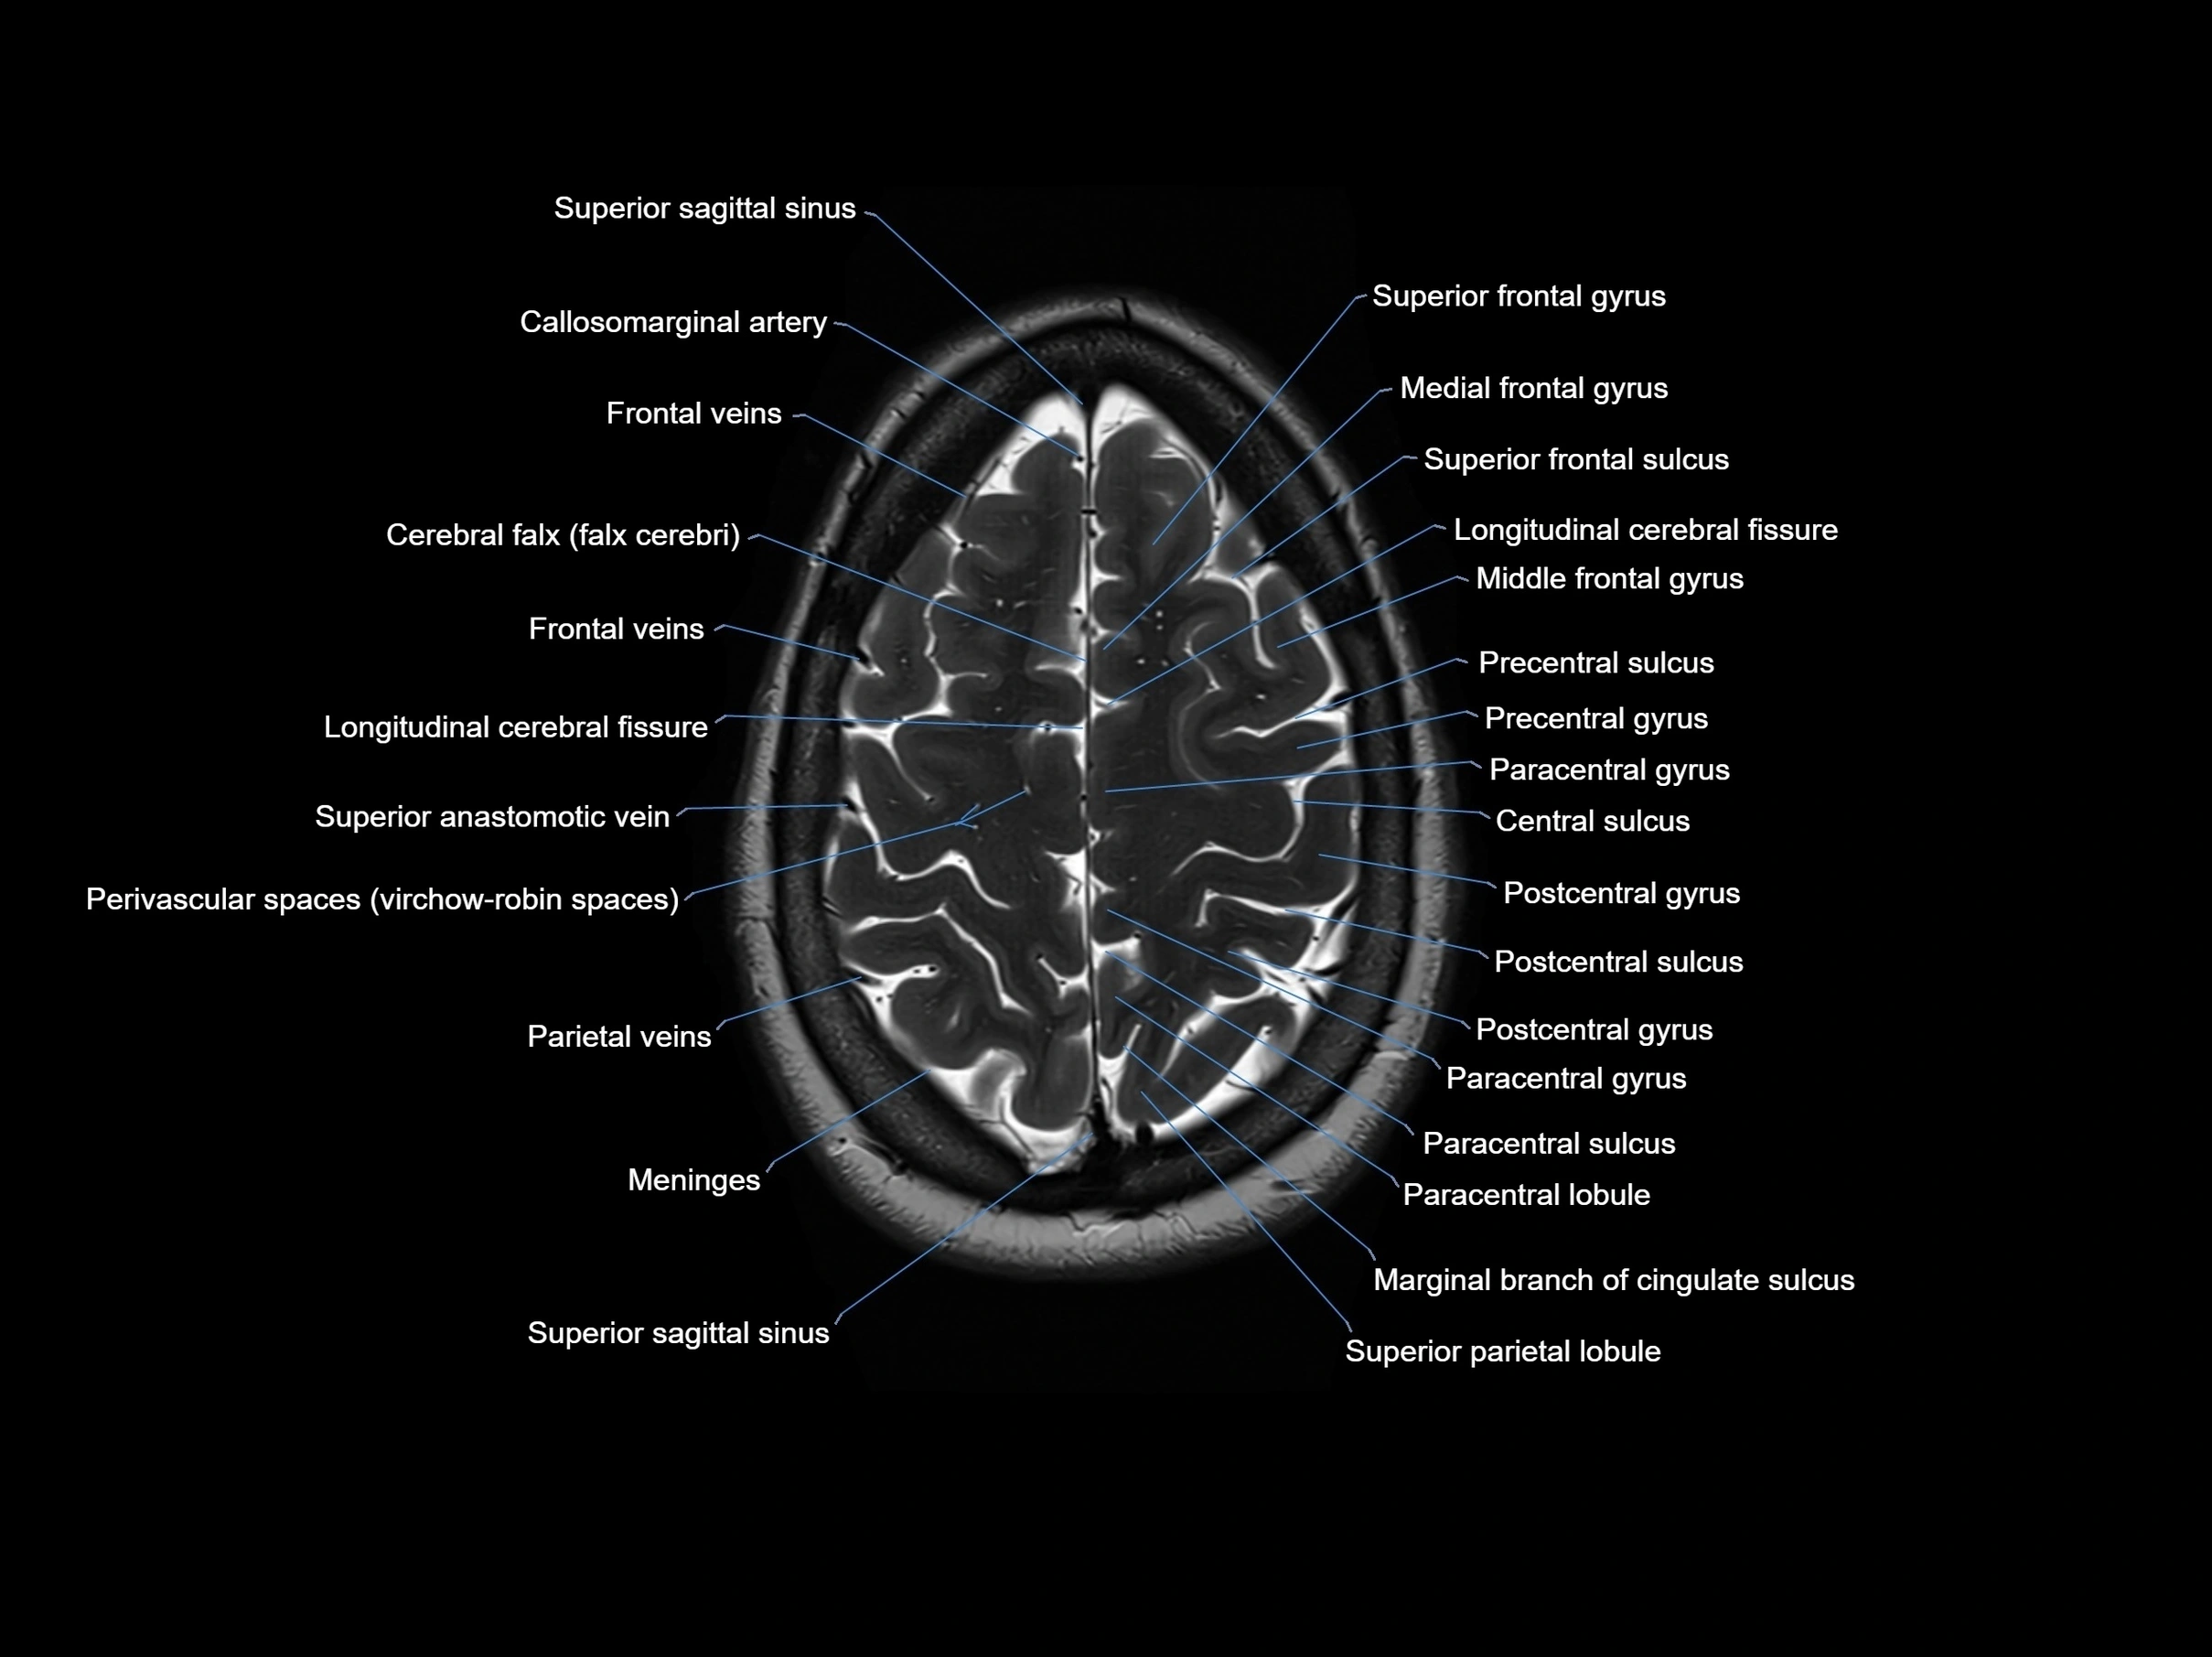

MRI images